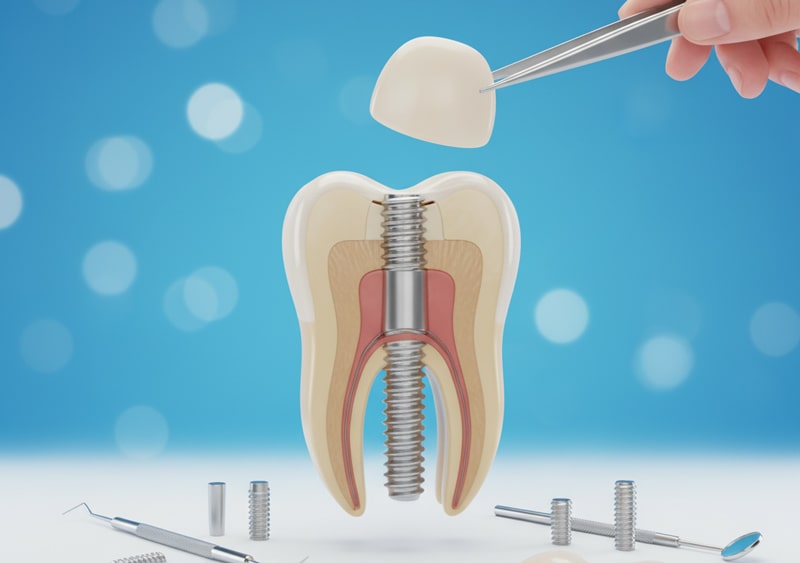

اگر دندان دچار درد، عفونت، شکستگی و دیگر مشکلات شود، سریعاً باید به دندان پزشک مراجعه کرد؛ دندان پزشک در ابتدا تمام تلاشش را می کند تا دندان طبیعی تان را با روش هایی مثل پرکردن یا عصب کشی حفظ کند. اگر مشکل از حد درمان های ساده گذشته باشد، پزشک روش های دیگری مثل ایمپلنت دندان یا پست و کور دندان و روکش را پیشنهاد می دهد. زمانی که دندان کامل از دست رفته باشد، باید آن را کشید و برای جایگزینی آن، می توان از کاشت دندان یا ایمپلنت استفاده کرد؛ ولی اگر تنها بخش زیادی از ساختار دندان از بین رفته باشد، با نصب پست به عنوان پایه و استفاده از تاج به عنوان روکش، ساختار دندان را تقویت می کنند. به صورت میانگین، برای ایمپلنت دندان باید بین ۸.۵ تا ۶۰ میلیون و برای پست حدود ۱ تا ۳ میلیون و برای روکش دندان حدود ۲ تا ۸ میلیون تومان هزینه پرداخت کرد.

ایمپلنت دندان زمانی بهترین گزینه محسوب می شود که دندان تان به طور کامل از بین رفته باشد؛ یعنی هم تاج و هم ریشه آسیب دیده و قابل ترمیم نیستند؛ در چنین شرایطی، دیگه روش هایی مثل پست و روکش پاسخگو نیستند، چراکه ریشه ای برای نگهداری وجود ندارد.

ایمپلنت یک جایگزین عالی و خیلی مشابه به دندان های طبیعی است. اگر چند دندان از دست داده اید یا می خواهید از دندان مصنوعی متحرک خلاص شوید، ایمپلنت می تواند جایگزینی عالی برایتان باشد.

برای کسانی که تراکم استخوان فک خوبی داشته و به سلامت لثه هایشان اهمیت می دهند، ایمپلنت یک انتخاب مطمئن با طول عمر بالا است؛ همچنین ایمپلنت برای افرادی که می خواهند زیبایی لبخندشان را بازگردانند یا از لق شدن دندان مصنوعی خسته شده اند، گزینه ای بی نظیر است. البته باید توجه داشت که این روش نیاز به صبر، هزینه نسبتاً بالا و رعایت دقیق بهداشت دهان و دندان دارد تا ایمپلنت سالم باقی بماند.

اگر ریشه دندان به طور کامل از بین رفته باشد، کشیدن دندان و کاشت ایمپلنت بهترین گزینه است، چرا که پایه آن، درون استخوان فک قرار گرفته و عملکردی مشابه دندان طبیعی دارد؛ اما اگر ریشه هنوز سالم است و فقط ساختار دندان، آسیب جدی دیده است، بهترین گزینه استفاده از پست یا روکش دندان است تا با کاشت پایه فلزی و نصب تاج، ساختار دندان را تقویت کرده و دندان طبیعی را حفظ کرد.

اگر دندان دچار مشکل شده باشد، برای درمان آن باید به دندان پزشک مراجعه کرد؛ دندان پزشک ابتدا سعی می کند تا با پر کردن دندان یا عصب کشی، دندان را درمان کرده تا دندان طبیعی حفظ شود؛ ولی اگر کار از این کار گذشته بود، باید دندان کشیده شود؛ پس از کشیدن دندان، باید جای آن را با گزینه دیگری پر کرد که این کار را می توان با انواع ایمپلنت انجام داد. به صورت میانگین، کاشت ایمپلنت در سال ۱۴۰۴، هزینه ای در حدود ۸.۵ تا ۶۰ میلیون تومان در پی دارد.